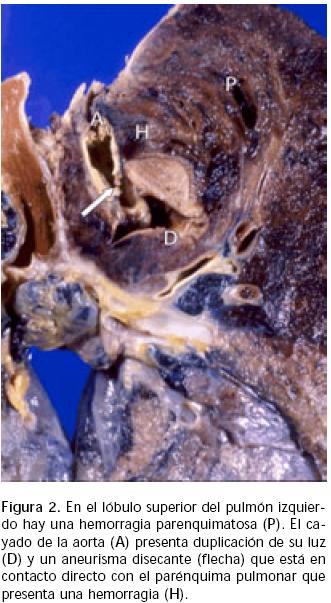

A las 48 h presentó nueva hemoptisis severa, hipotensión y dificultad respiratoria, colocándose entonces sonda endotraqueal para aspiración, se instaló ventilación mecánica y se administraron plasma y paquete globular; por fibrobroncoscopía, se observaron tráquea y bronquios principales con algunos coágulos pequeños. En la toracentesis se obtuvo líquido hemático. Se sospechó la posibilidad de un aneurisma aórtico abierto a cavidad pleural izquierda. Se administraron betabloqueadores y más hemoderivados, pero continuó con hipotensión arterial y dificultad respiratoria. A las 72 h de su ingreso presentó paro cardíaco irreversible consecutivo a taquicardia y fibrilación ventriculares. La necropsia demostró la presencia de 1,500 mL de sangre y coágulos en cavidad torácica izquierda; el cayado de la aorta se encontró en contacto con el lóbulo superior del pulmón izquierdo que presentaba una hemorragia en la división superior, donde se localizó una comunicación entre la pared aórtica y el parénquima pulmonar; esta lesión también estaba en comunicación con la cavidad pleural (Figura 2). El estudio microscópico demostró la separación de la capa muscular aórtica del endotelio en el canal correspondiente a un aneurisma disecante de 7 cm de extensión, sin alteraciones en el tejido conectivo (Figura 3).

El hemotórax izquierdo14, en ocasiones derecho3, puede ser consecutivo a un aneurisma disecante de aorta descendente; en el presente caso, el aneurisma partió de una lesión localizada en el cayado de la aorta que se comunicaba con el lóbulo superior del pulmón izquierdo y la cavidad pleural (Figuras 2 y 3), ocasionando la hemoptisis y el hemotórax izquierdo.